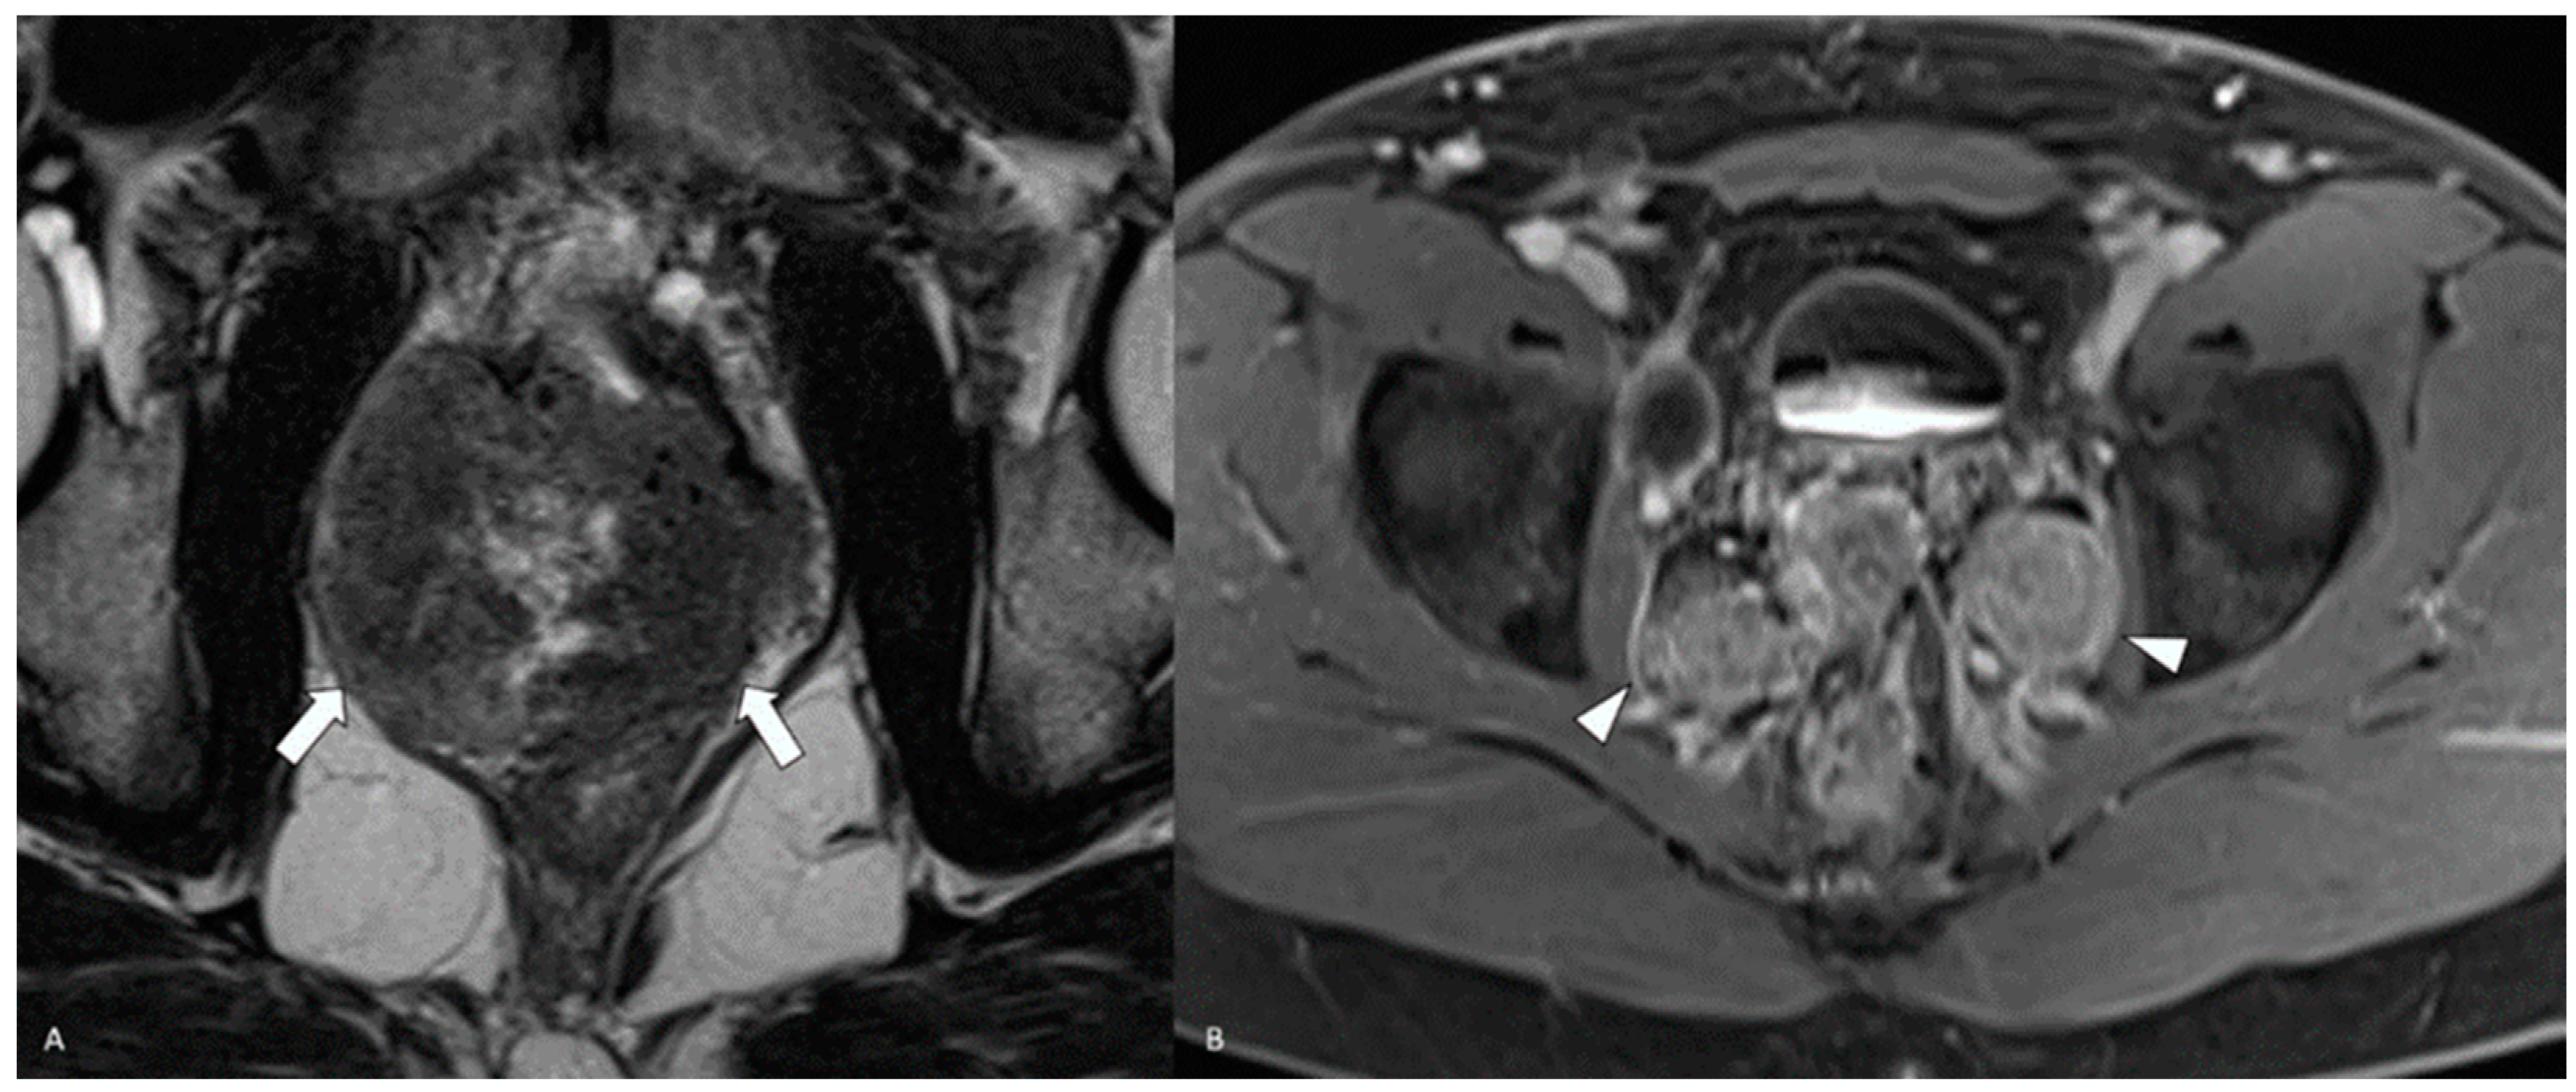

- Yang, J.; Xiao, L.; Gao, X.; Tang, Y.; Hu, S. Primary Adenosquamous Carcinoma of the Prostate With Multiple Heterogenic Metastases Demonstrated on 68Ga-PSMA and 18F-FDG PET/CT Imaging. Clin. Nucl. Med. 2024, 49, 180–181. [Google Scholar] [CrossRef] [PubMed]